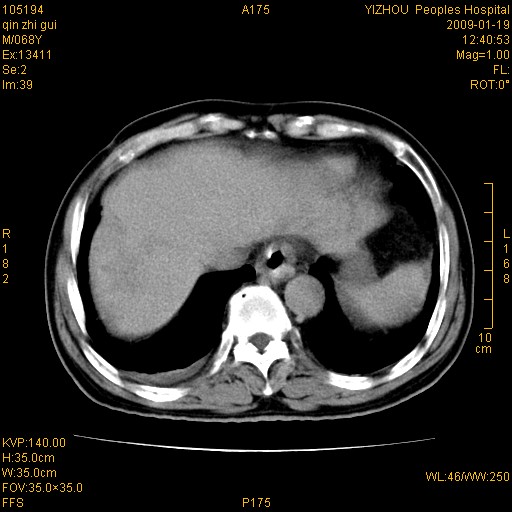

以下是引用随光逐影在2009-1-21 16:11:00的发言:[br]1)考虑肝右叶肝癌并肝静脉及门静脉瘤栓形成。2)肝硬化,少量腹水。3)胆囊炎。4)右侧少量胸腔积液。

病灶外缘凹凸不平,平扫低密度,增强动脉期有强化,门脉早显,静脉期及延期呈延迟强化,结合病史考虑右肝前叶巨块型肝癌可能性大,强化表现不除外胆管细胞癌